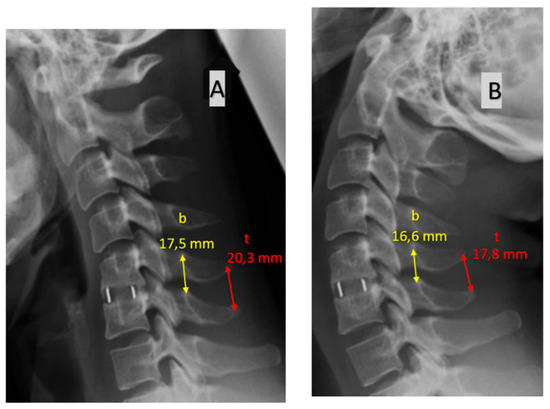

- change in the distance (in millimetres) between the bases of spinous processes in flexion vs. extension. Values ≥2 mm are considered a sign of fusion while values <2 mm represent a pseudoarthrosis.

- change in the distance (in millimetres) between the tips of spinous processes in flexion vs. extension. The threshold values are the same as with the 1st method above.